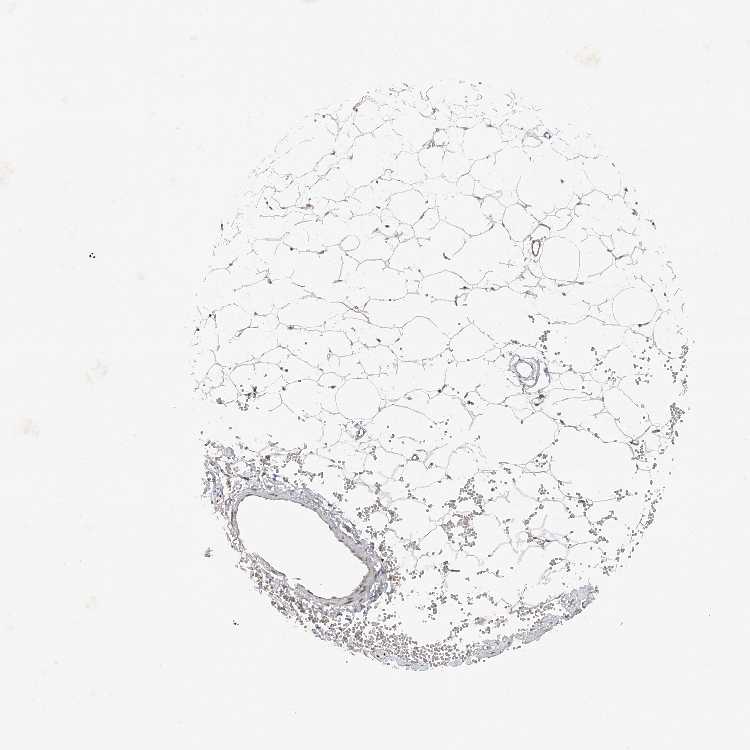

SOFT TISSUE 1 - Antibody stainingi

Antibody staining in the annotated cell types in the current human tissue is reported as not detected, low, medium, or high, based on conventional immunohistochemistry profiling in selected tissues. This score is based on the combination of the staining intensity and fraction of stained cells.

Each image is clickable and will lead to virtual microscopy that enables deeper exploration of all samples and also displays staining intensity scores, fraction scores and subcellular localization as well as patient and tissue information for each sample.

Antibody HPA028882

Chondrocytes Medium

Fibroblasts Low

Peripheral nerve Low

SOFT TISSUE 2 - Antibody stainingi